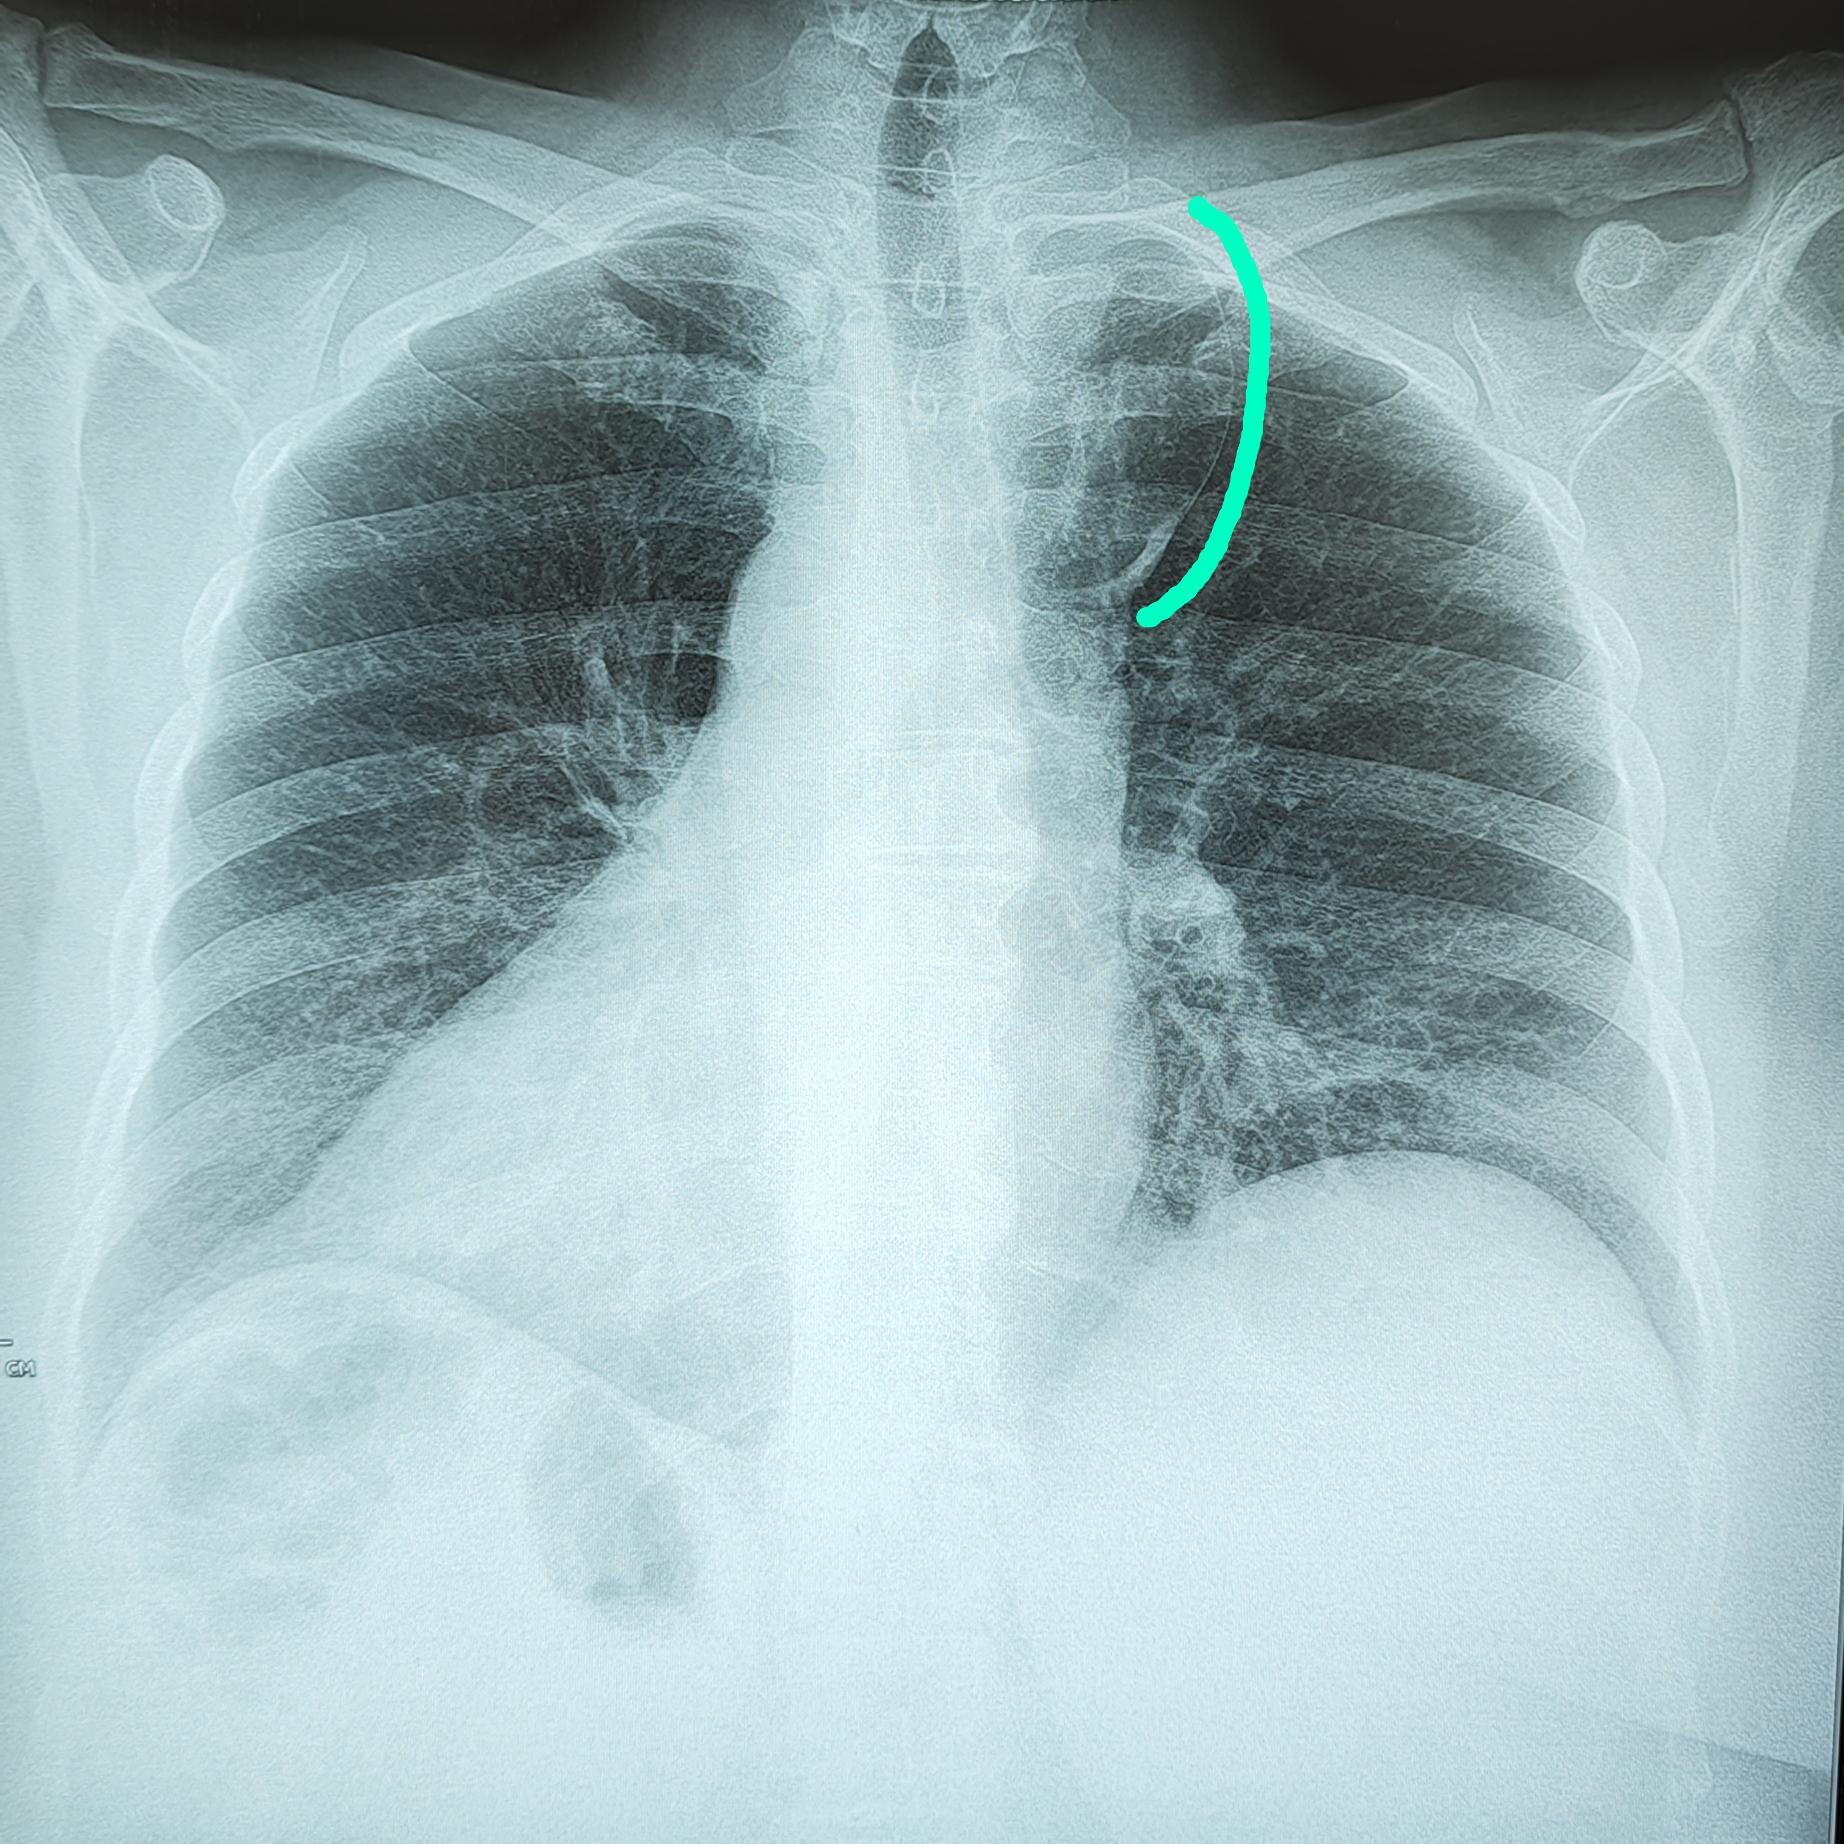

Справа по парастернальной линии, чаще на уровне 1-го межреберья (иногда на уровне хрящевой части 1 или 2-го ребер) определяется небольшая в форме вытянутой капли тень (от 0,3 до 0,8 мм ширины и от 0,6 до 2,5 мм длины) с четкими контурами. Эта «капля», заостряясь кверху, переходит в нежную (волосяную) линейную тень добавочной междолевой щели; она направлена кверху и дугообразно изгибается выпуклостью кнаружи.